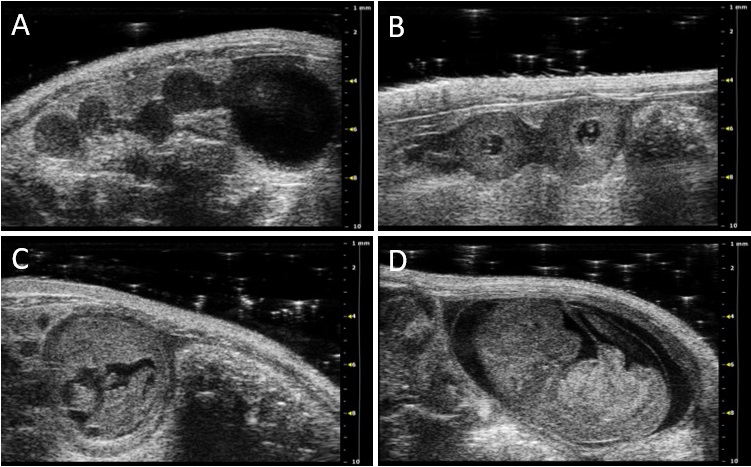

It can be used for various research fields like cardiology, development, molecular imaging, oncology, neurobiology, urogenital and vascular biology as well as pregnancy research[1]. Furthermore, the influence of environmental chemicals can be impressively investigated in vivo. Ultrasound is a standard method during pregnancy. Fetal developmental disabilities or impairments can be recognized early. The VEVO 2100 Imaging System enables us to analyze fetuses and placentas in pregnant mice in vivo (Figure 2, 3). Moreover, we can follow–up fetal as well as maternal blood flow parameters throughout pregnancy (Figure 4). The technique is important to assess intrauterine growth restriction, a pregnancy complication with short- and long-term health consequences for both mother and fetus. The high utility of this method is exemplified by its non-invasiveness and the possibility to analyze the same animal throughout pregnancy, without sacrificing several animals at different gestational days[2,3]. 2D grey-scale ultrasound images Figure 2: 2D grey-scale ultrasound images showing implantation areas from mice at gestation day (gd) 5 (A), gd8 (B), gd10 (C), and gd12 (D). Figure republished from [3]. 2D grey-scale ultrasound images Figure 3: (A) 2D grey-scale ultrasound image of an implantation at gestation day (gd) 10 showing decidua basalis, placenta, embryo. (B) 2D grey-scale ultrasound image of an implantation at gd12 showing placental thickness (thick) and placental diameter (dia). Figure republished from [3]. Color Doppler image and Pulse-wave Doppler image Figure 4: Color Doppler image of a fetal umbilical artery at gestation day (gd) 14. (B) Pulse-wave Doppler images of a maternal uterine artery at gd10 showing peak systolic velocity (PSV) and end diastolic velocity (EDV). Figure is republished from [3].